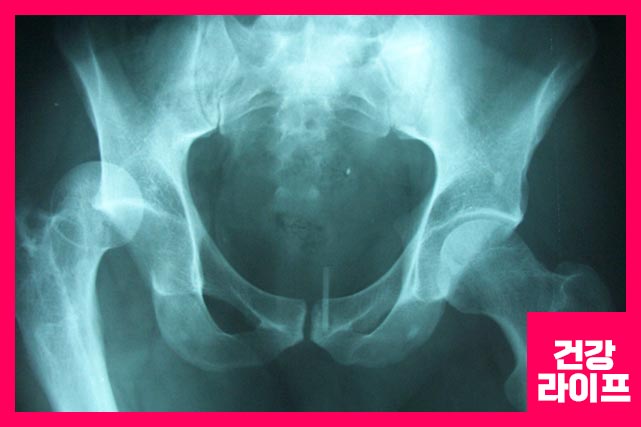

고관절은 볼기뼈의 절구와 넙다리뼈 머리 사이의 활액 관절입니다. 해당 관절은 몸의 안정성과 체중 부하를 위한 기능을 합니다. 구조는 세 가지 유형입니다.

골절

대퇴골 위쪽 1/4이 부러지는 것을 고관절 골절이라고 합니다. 과격한 운동, 낙상(옆으로 넘어졌을 때) 생깁니다.